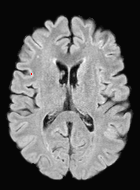

Patch size is another important parameter of the network. In computer vision applications such as object detection, usually a whole 2D image is used as a feature. However, full 3D medical images can not typically be used because of memory limitations. Fig. 4 shows examples of lesion memberships obtained with different sized 2D patches. As the patch sizes increases, the false positives that are mostly observed in the cortex tend to decrease. Fig. 5 shows a plot of Dice and LFPR with various patch sizes, ordered from left to right according to their increasing size. Note that smaller patches ( to ) produced significantly lower Dice and higher LFPR compared to other patches (), as seen from the memberships in Fig. 4. Also some of the highest Dice and lowest LFPR were observed for patches with large in-plane size, i.e., , , and . It was observed in Fig. 5 that there is no significant difference between Dice coefficients for , , or , but LFPR of both and are significantly lower than that of (). We chose as the optimal patch size. Other choices of smaller and patches (not shown) yielded worse results. Note that although training was performed with different patch sizes, the memberships were generated slice by slice, as the trained model consisted only of convolutions and did not need any information about patch sizes.

In our experiments, we used large 2D patches similar to Ghafoorian et al. (2017b), in comparison to isotropic 3D patches as used before, e.g., in Valverde et al. (2017), in Wachinger et al. (2017), and in Kamnitsas et al. (2017). The rationale behind using large anisotropic patches is twofold. First, experiments with full 3D isotropic or patches showed little or no improvement in Dice and led to increased false positives, with memberships similar to the one with patches, as shown in Fig. 4. Larger isotropic patches, e.g. or , showed inferior segmentation, and in some cases, optimization did not converge. The reason is that the FLAIR images in the test datasets had inherently low resolution in the inferior-superior direction, mm and mm compared to in-plane resolution of mm. Therefore 2D axial patches capture the high resolution in-plane information that represents the original thick axial slices. Second, the lesions are usually focal and small in size, unlike other brain structures. Therefore a very large isotropic patch around a small lesion can include superfluous information about the lesion, which can increase the amount of false positives. Note that with in more recent studies employing high resolution 3D FLAIR sequences, it is trivial to extend the algorithm to accommodate for 3D patches.